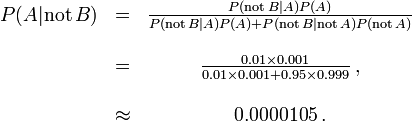

In order to reduce the problem of false positives, a test should be very accurate in reporting a negative result when the patient does not have the disease. If the test reported a negative result in patients without the disease with probability 0.999, then

,

,

so that  now is the probability of a false positive.

now is the probability of a false positive.

On the other hand, false negatives result when a test falsely or incorrectly reports a negative result. For example, a medical test for a disease may return a negative result indicating that patient does not have a disease even though the patient actually has the disease. We can also use Bayes' theorem to calculate the probability of a false negative. In the first example above,

The probability that a negative result is a false negative is about 0.0000105 or 0.00105%. When a disease is rare, false negatives will not be a major problem with the test.